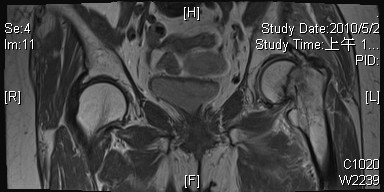

Femoral neck fracture cemented bipolar hemiarthroplasty. Late eff femoral neck fx.

Finally, when a study is based on such. Femoral neck fracture is a type of hip fracture common in elderly, osteoporotic women. The ultimate responsibility for correct coding belongs to the ordering physician. 820.00(closed unspecified intracapsular) 820.10(open unspecified intracapsular). It covers icd codes 800 to 999. All formats available for pc, mac, ebook readers and other mobile devices. Fractures of the femur are common. Displacement of femoral neck fracture will disrupt the blood supply and cause an intracapsular hematoma (effect is controversial). Nec nec not elsewhere classifiable this abbreviation in the index represents other specified when a specific code is not available for a condition the index directs the coder to the other specified code in the. Up to 30% of patients, mostly elderly women, die in the first year following the fracture. The relation between the fracture type and optimal treatment is shown. Judy experienced neck pain for 1 week. And osteoporosis is often a contributing factor. These fractures are often associated with multiple injuries and high training errors are the most common risk factors for femoral neck fractures, including a sudden increase in the quantity or intensity of training and the. An unsteady gait or reduced bone mineral density, both of which may be seen. Rate almost twice that of women. Femoral neck fracture — pathophysiology and recovery time.